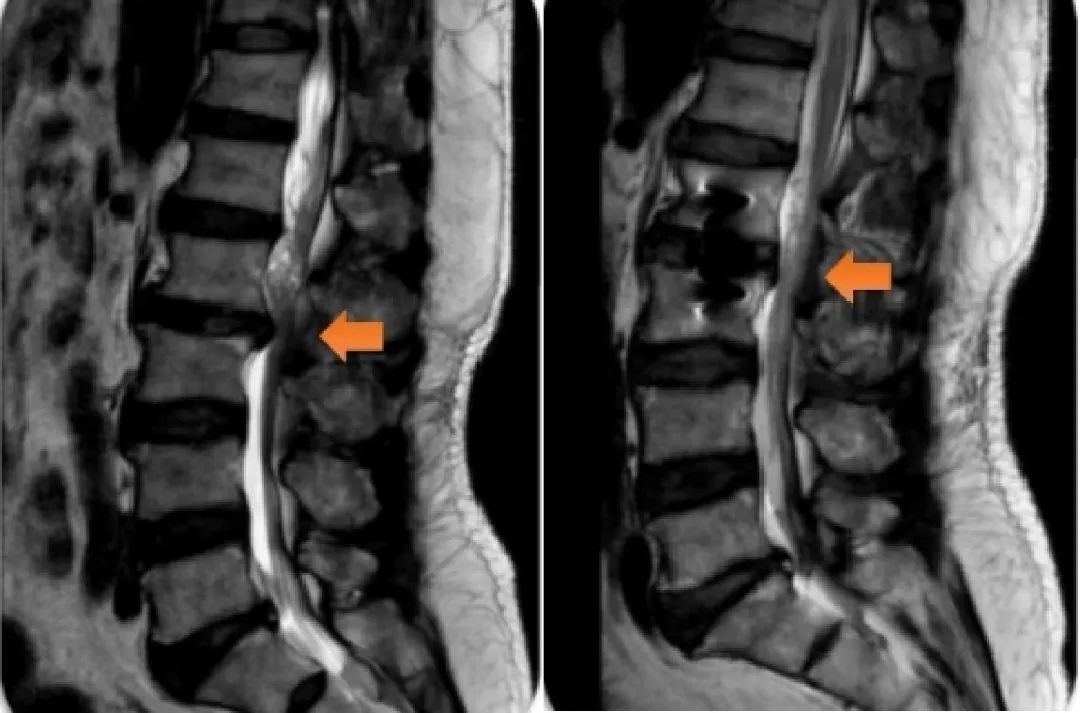

患者手术前后影像检查图,橙色箭头为颈椎狭窄处

经过仔细询问病史,这位患者常年伏案工作,近年来常感颈部不适。再一查体,病理反射很明显,医生初步考虑不是脑梗,而是颈椎问题。再经过颈椎MRI检查,最终明确诊断为脊髓型颈椎病,建议住院手术治疗。